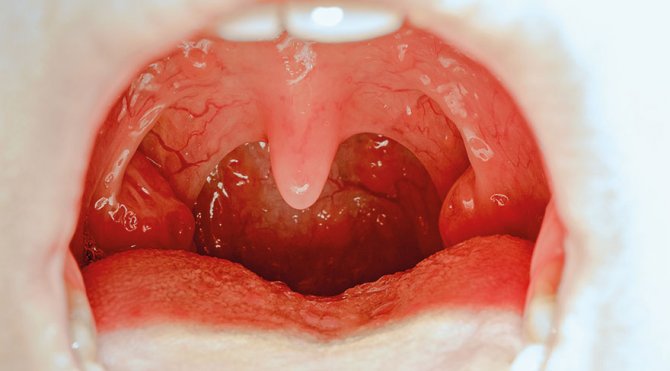

Bilim dünyasında doğurganlığa ilişkin ilginç bir veriye ulaşıldı. Yapılan bir araştırmada apandisit ameliyatı olmuş ve bademciğini aldırmış kadınların hamile kalma şansız yüzde 50’den fazla artıyor.

Doğurganlık arasındaki bağlantı henüz çözülemese de bu ameliyatlardan birini ya da her ikisini birden olmuş olan kadınlarda doğurganlık artıyor. Doğurganlık, apandisit ameliyatı olan kadınlarda yüzde 54.4, bademciklerini aldıran kadınlarda ise yüzde 53.4 oranında artarken her iki ameliyatı olmuş kadınlarda yüzde 59.7 oranında daha fazla.

Dundee Üniversitesi Tıp Fakültesi’nde yapılan bu araştırma ile ilgili Dr. Sami Shimi şu yorumu yaptı: “Yıllarca apandisit ameliyatının tam tersi etki yaptığı düşünülüyordu… Ancak bunun neden doğurganlığı arttırdığını tam olarak bilmiyoruz. O nedenle bu bir kısırlık tedavisi olarak düşünülemez. Kadınlar kesinlikle bilinen kısırlık tedavilerini bırakarak bu ameliyatları olmayı denememeli.”